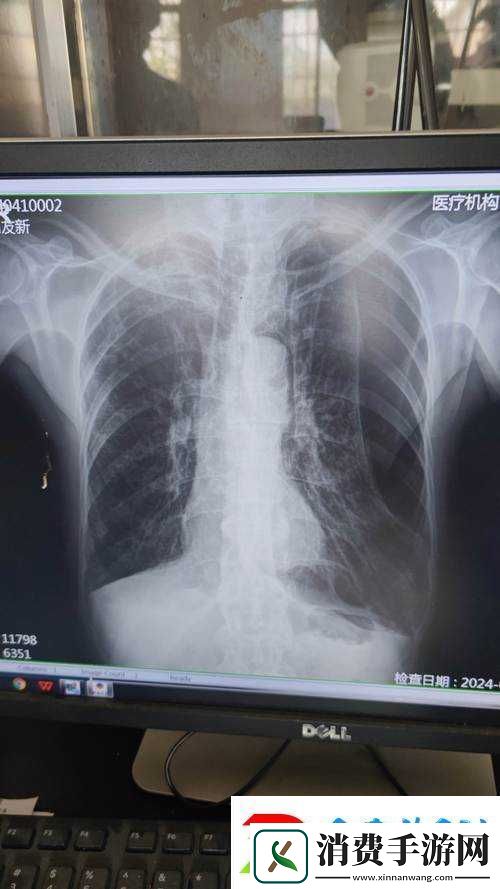

让我们来看看胸片 100%曝光下的图像。这些图像通常呈现出人体内部的骨骼、肺部和其他组织的细节。当我们仔细观察这些图像时,会发现一些不寻常的现象。例如,在某些胸片中,我们可以看到肺部呈现出一种暗淡的红色,这可能是由于肺部感染或其他疾病引起的。在其他胸片中,我们可以看到肺部呈现出一种强烈的红色,这可能是由于情绪激动或其他原因引起的。

接下来,让我们来探讨胸片 100%曝光下愤怒的情绪直观呈现。当我们处于愤怒情绪时,身体会释放出一系列的生理反应,如心跳加快、血压升高、呼吸急促等。这些生理反应会影响我们的身体和心理状态。在胸片 100%曝光下,我们可以看到这些生理反应在肺部的表现。例如,在愤怒情绪下,肺部的血管会扩张,肺部的颜色会变得更加鲜艳,这可能是由于血液供应增加引起的。

胸片 100%曝光下愤怒的情绪直观呈现还可以通过其他方式表现出来。例如,在某些胸片中,我们可以看到肺部的纹理变得更加混乱,这可能是由于情绪激动引起的肺部肌肉紧张引起的。在其他胸片中,我们可以看到肺部的形状发生变化,这可能是由于情绪激动引起的呼吸方式改变引起的。